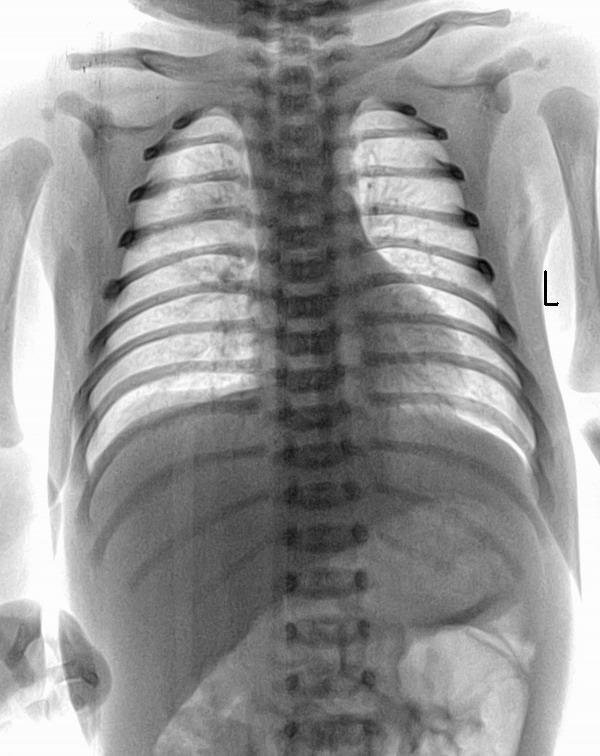

男 11天 主诉:呛咳后咳嗽,呼吸困难2天。查体:双肺呼吸音粗,可闻及明显水泡音

右肺上野考虑吸入性肺炎

新生儿肺炎,肺气肿,纹理重,右上淡片影.

右肺上野可见淡片状阴影,边不清,结合病史考虑吸入性肺炎。

双肺纹理增强,右肺中上野内中带示淡薄云絮状阴影,结合病史考虑吸入性肺炎。

右肺炎症,请仔细询问呛咳史,警惕支气管异物。